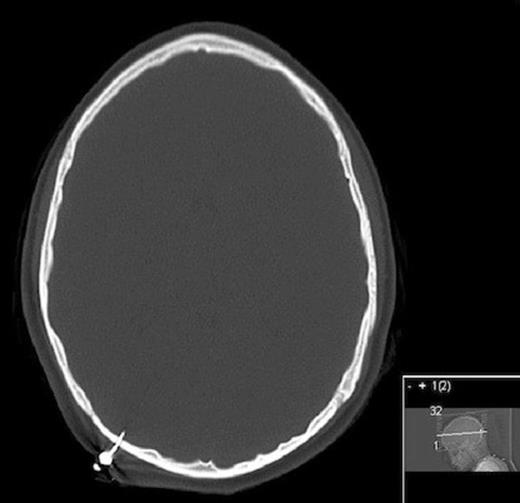

CT scan of the head revealed the dart to have traversed the inner and outer tables of the skull, with a portion extending intracranially (Figure 2).

CT head bone windows showing penetration through inner and outer tables of skull intracranially